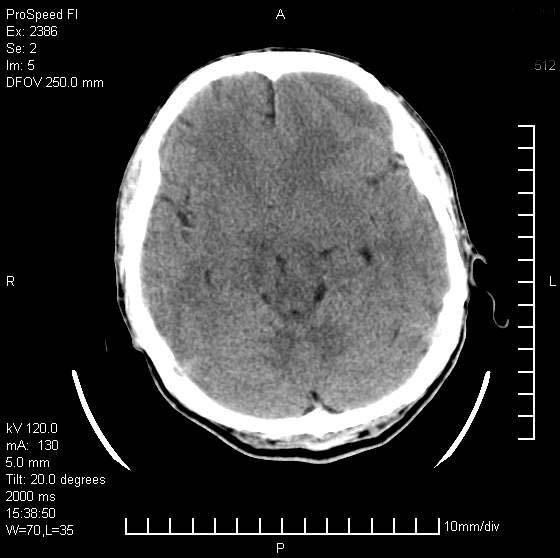

以下是引用天南地北在2007-9-19 18:43:00的发言:[br]典型慢性硬膜外血肿[br][br][本贴已被 天南地北 于 2007-9-19 18:44:11 修改过]

以下是引用曼一拍在2007-9-20 11:06:00的发言:[br]支持慢性硬膜下血肿.[br]慢性硬膜下积液:血肿有包膜,ct值稍高于脑脊液,增强可有染色。不典型者血肿可多呈梭形.是硬脑膜与蛛网膜之间的潜在腔隙内的血肿。[br]鉴别:[br]1\\硬膜外血肿:是颅脑外伤后脑膜或板障内血管破裂,血液在颅骨与硬膜之间积聚所致.通常是脑膜动脉破裂,也可因静脉窦破裂或颅骨的板障静脉出血,发生于外伤的着力部,常与颅骨骨折并存。脑膜动脉出血则急,若是板障静脉出血在则可有慢性。[br]2\\硬膜下积液:(硬膜下水瘤)[br]是由于蛛网膜破裂,脑脊液经蛛网膜破口进入硬膜下腔不能回流。或水肿阻塞而形成。[br]ct表现:颅骨内板下方新月形低密度区近似脑脊液密度;占位效应清,周围无脑水肿。[br]